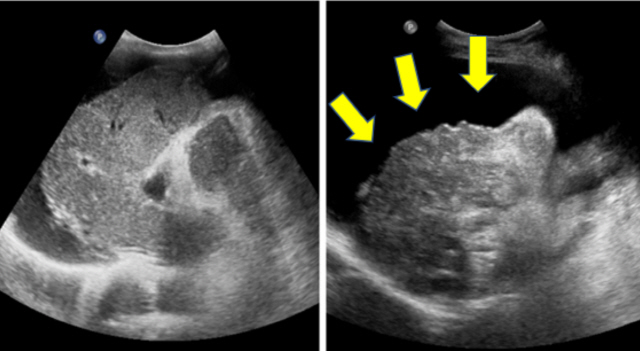

간경화가 어느 정도 진행이 돼서 복수가 차는 증상이 나타나게 되었다면 이뇨제를 동원해 조절하게 됩니다. 하지만 이뇨제를 사용해겠지만 호흡이 곤란하고 복부에 통증이 나타난 경향이라면 복수 천자를 시행하는데, 복수 천자가 가장 빠르고 효과가 좋은 방법이라고 합니다. 복수 천자는 주사기를 활용해서 직접 배에서 복수를 빼내는 방법이라고 할 수 있다하며, 이 방법은 바로 복수가 빠지었으므로 복수로 인한 불편함은 빠르게 해소되지만 잠정적인 방법이라서, 일정 기간이 경화하다 보면 복수는 다시 차게 되기 때문에 복수를 되풀이해서 빼주어야 합니다. 또한 복수가 있는 간경화를 앓는 환자들 중 자발성 세균성 복막염이 생기게 되는 상황가 있다고 하는데, 이 경우에는 항생제를 이용해서 치료하게 되기도 합니다. 세밀한 것은 내방하셔서 전문의와 상의하는 것을 권유해 드려볼께요 할게요.